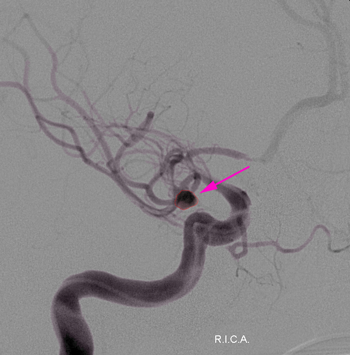

Aneurysm1

Ανεύρυσμα (περίγραμμα)